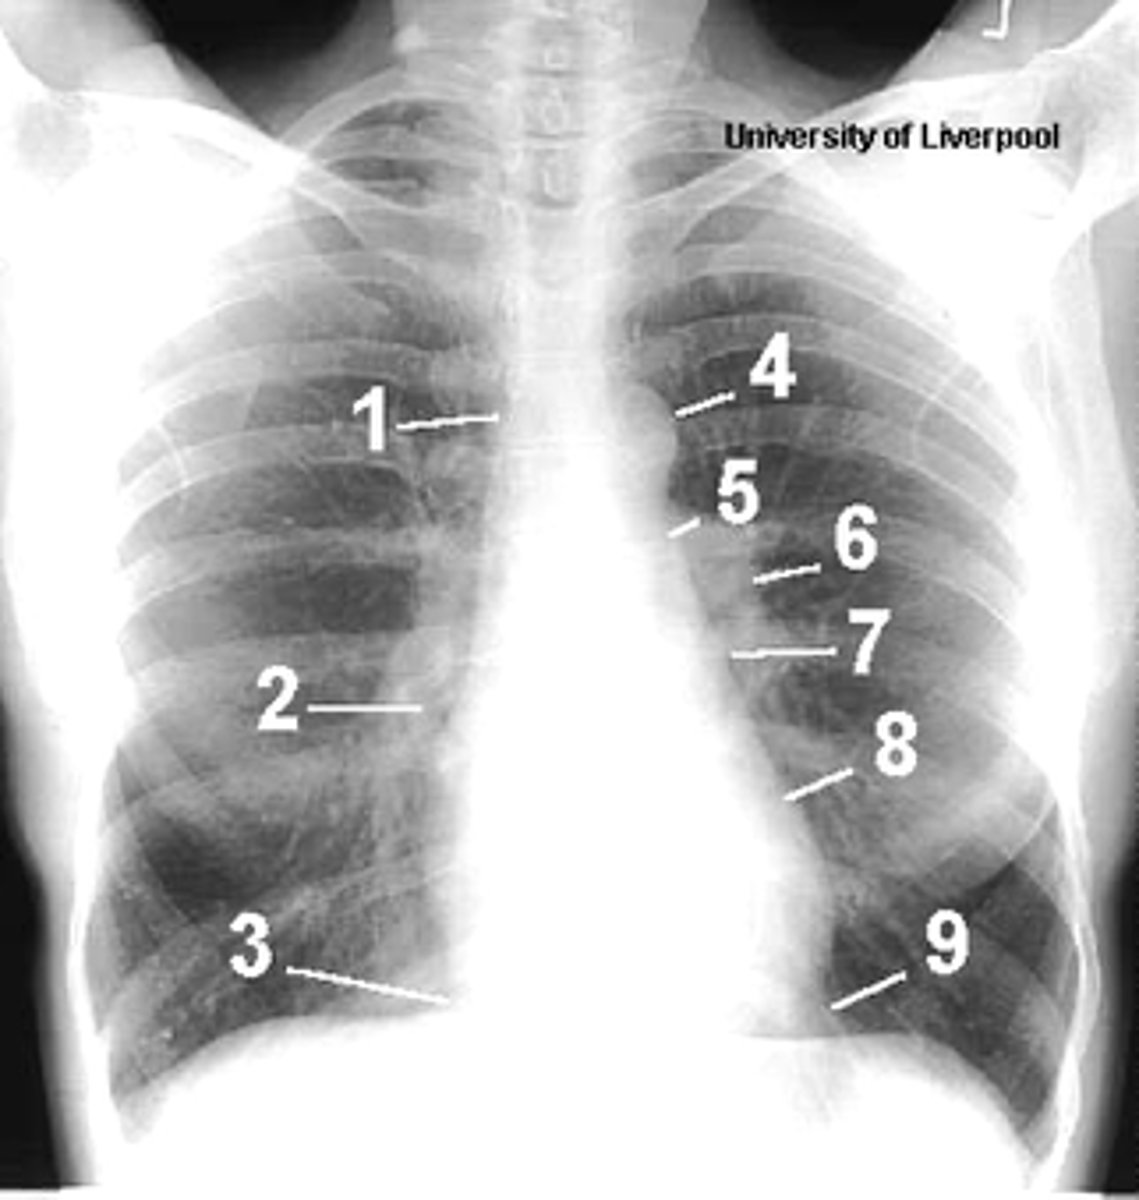

1

superior vena cava

2

right atrium

3

inferior vena cava

4

aortic arch or knob

5

left pulmonary trunk

6

left pulmonary artery

7

left atrium

8

left ventricle

9

left cardiophrenic angle